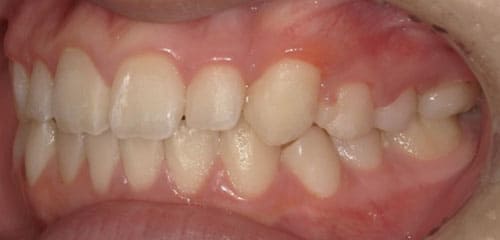

● 歯根が折れ保存不可の歯を抜歯して、そのスペースに八重歯を並べた症例

藤沢デンタルオフィスの虫歯や破折で抜歯後の部分矯正